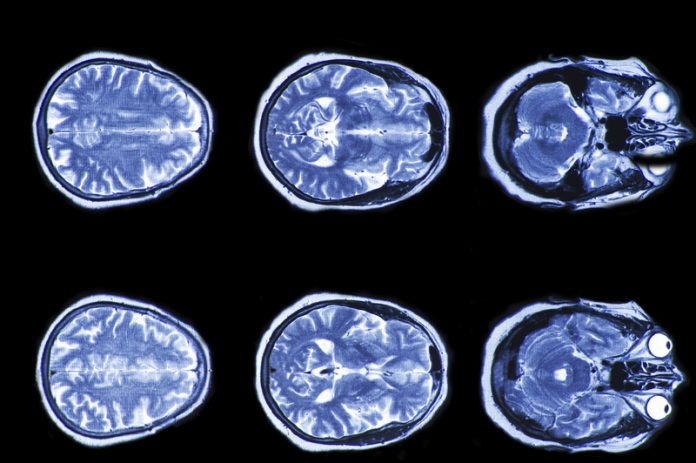

The breakthrough could have implications for treatment of neurodegenerative illnesses such as Alzheimer’s, or in the treatment of more minor brain injuries.

Bernhat believes mapping how the pathways of the brain map normal consciousness could improve our understanding.